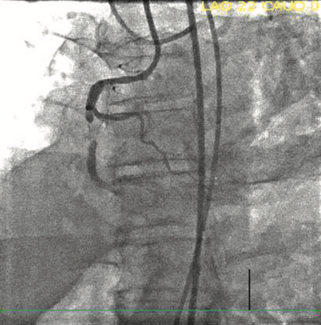

Coronary artery perforation (CAP) is a rare but serious, and potentially fatal, complication of percutaneous coronary intervention (PCI). CAP occurs when an intimal tear or dissection penetrates the arterial wall. Previous studies estimate...

Constrictive pericarditis is a morbid condition, with a challenging diagnosis. Because constrictive pericarditis is generally considered a treatable cause of heart failure, evaluating for and distinguishing constrictive pericarditis from...